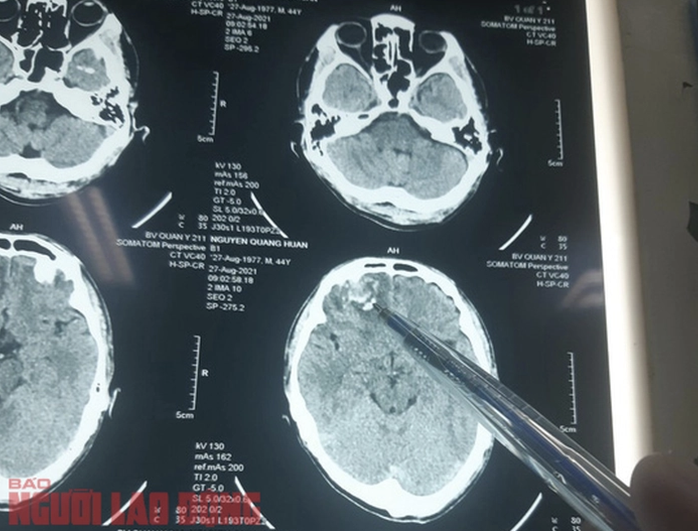

Ông Nguyễn Quang Huấn bị chấn thương sọ não, dập não, tụ máu trong não, chấn thương phần mềm vùng chẩm…

Ngày 27-10-2021, Cơ quan Cảnh sát điều tra, Công an huyện Chư Sê đã gửi thông báo Kết luận giám định cho ông Huấn. Theo kết luận này, tỉ lệ tổn thương cơ thể của ông Huấn do thương tích gây nên tại thời điểm giám định là 35%.